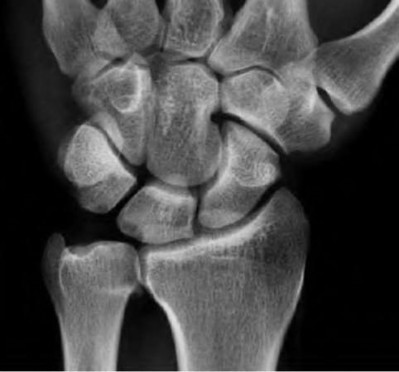

A 22-year-old male falls onto an outstretched hand and sustains a displaced fracture through the proximal pole of the scaphoid. Avascular necrosis of the proximal pole is highly likely due to the disruption of its primary vascular supply. Which vessel provides this critical retrograde perfusion?

Explanation

The primary blood supply to the scaphoid is from the dorsal carpal branch of the radial artery, which enters the dorsal ridge of the scaphoid at the waist and courses proximally. This retrograde blood flow makes proximal pole fractures highly susceptible to avascular necrosis and nonunion. The superficial palmar branch provides a minor supply (about 20%) to the distal pole.